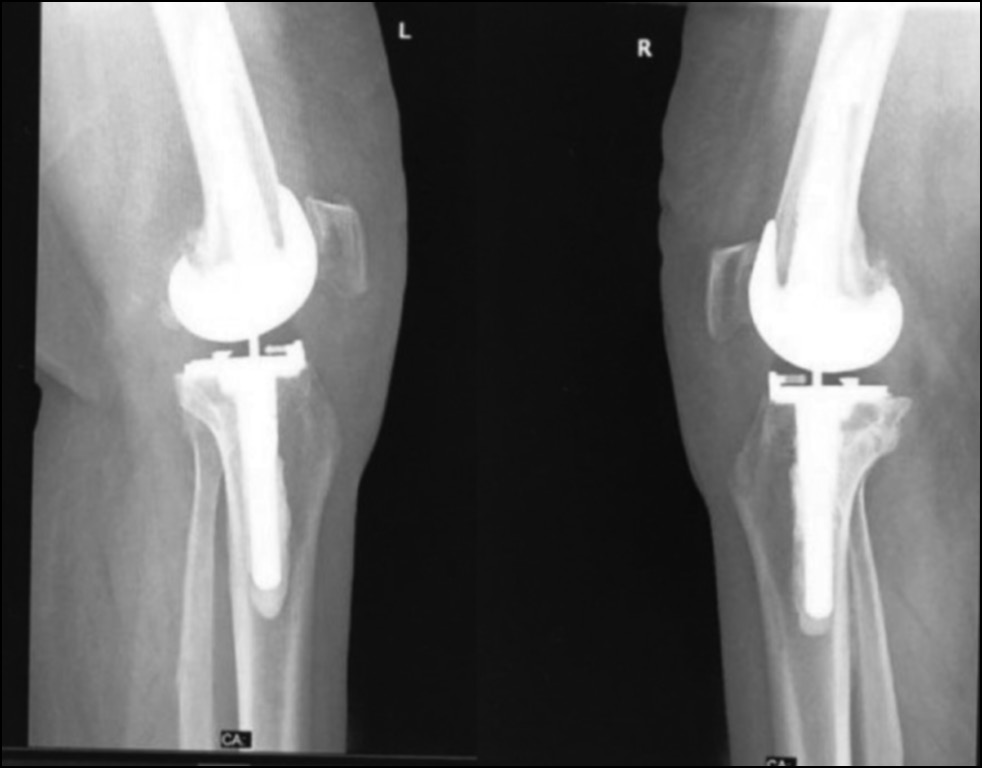

Fig. 15. Ap preoperative x-ray showing bilateral knee osteoarthritis.

Рис. 15. Предоперационная рентгенограмма с двусторонним остеоартритом коленного сустава.

Fig. 16. Lateral preoperative x-ray right and left knees showing osteoarthritis.

Рис. 16. Предоперационная боковая рентгенограмма правого и левого колена с признаками остеоартрита.

CASE 2. PATIENT 3

Age: 67 years.

Sex: Female.

Diagnosis: Bilateral advanced knee osteoarthritis.

Procedure: Bilateral simultaneous knee arthroplasty.

Associated illnesses: DM and hypertension.

Postoperative follow-up: No postoperative complications were encountered.

Length of hospital stay: 6 days.

Radiological assessment (Fig. 15–18)